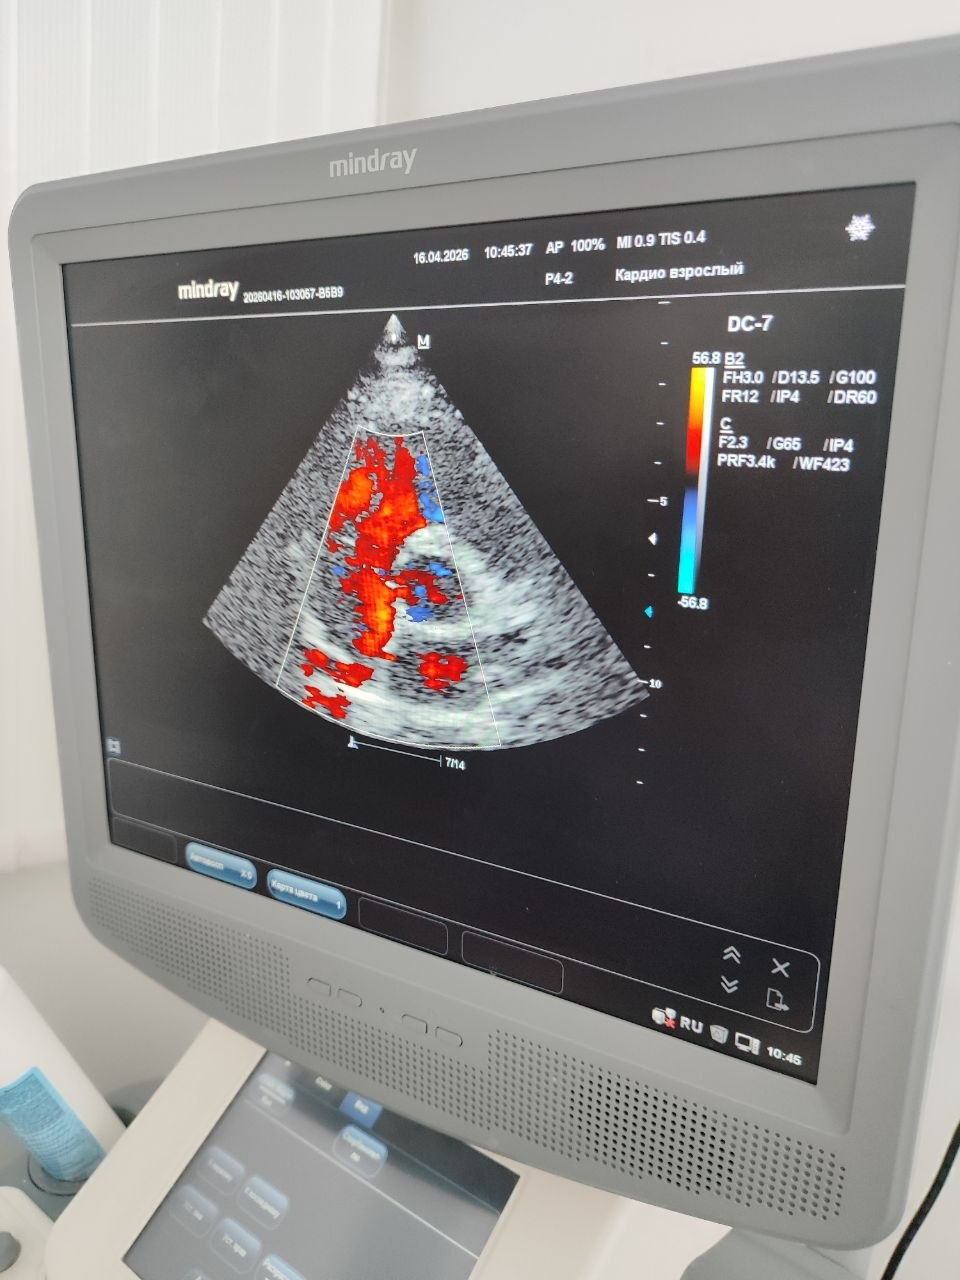

Главный сюрприз ждал ребят во время практической части. Наталья Борисовна и Кирилл организовали для группы экскурсию в кабинет РКТ (рентгеновской компьютерной томографии), а затем переключили внимание на ультразвуковые методы исследования. Под чутким руководством студента-дублёра и Натальи Борисовны каждый участник занятия получил уникальную возможность попробовать себя в роли врача ультразвуковой диагностики. Ребята освоили базовые протоколы сканирования: щитовидной железы, слюнных желез, почек и печени.

Настоящим подарком для студентов стал мастер-класс по эхокардиографии от Натальи Борисовны Кривелевич, которая продемонстрировала тонкости исследования сердца.